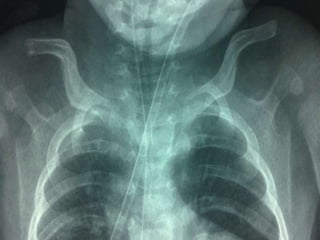

61 years old man with epigastric pain and vomiting

Caffey disease(ICH)AD  .subperiosteal bone formationbefore 6 months, M:f  1:1General hyperirritability, fever and anorexia, painful, firm soft-tissue swelling.PGETTT infants with cyanotic heart disease cortical hyperostosis that mimics ICH. PGE serum levels elevated Indomethacin.

61 years oldman with epigastric pain and vomiting